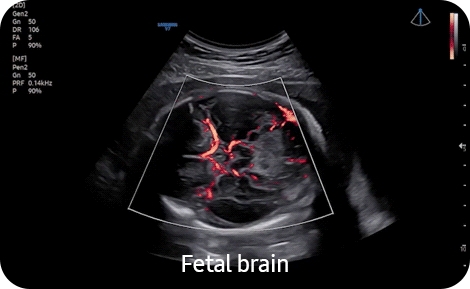

• Высокочувствительный направленный энергетический допплер S-Flow позволяет визуализировать даже самые мелкие сосуды

• 5D CNS+- Модуль автоматического получения 9 стандартных поскостей головного мозга плода и последующих автоматических измерений стандартных параметров фетометии головного мозга плода 5D CNS из объемных данных. Необходим модуль 4D. (CV1-8AD);

• 5D Heart Color- Модуль автоматического получения 9 стандартных плоскостей сердца плода из объемных данных STIC в соответствии с международными методическими рекомендациями с динамическим отображением кровотока 5D Heart Color. Необходим модуль 4D. (CV1-8AD, EV2-10A);